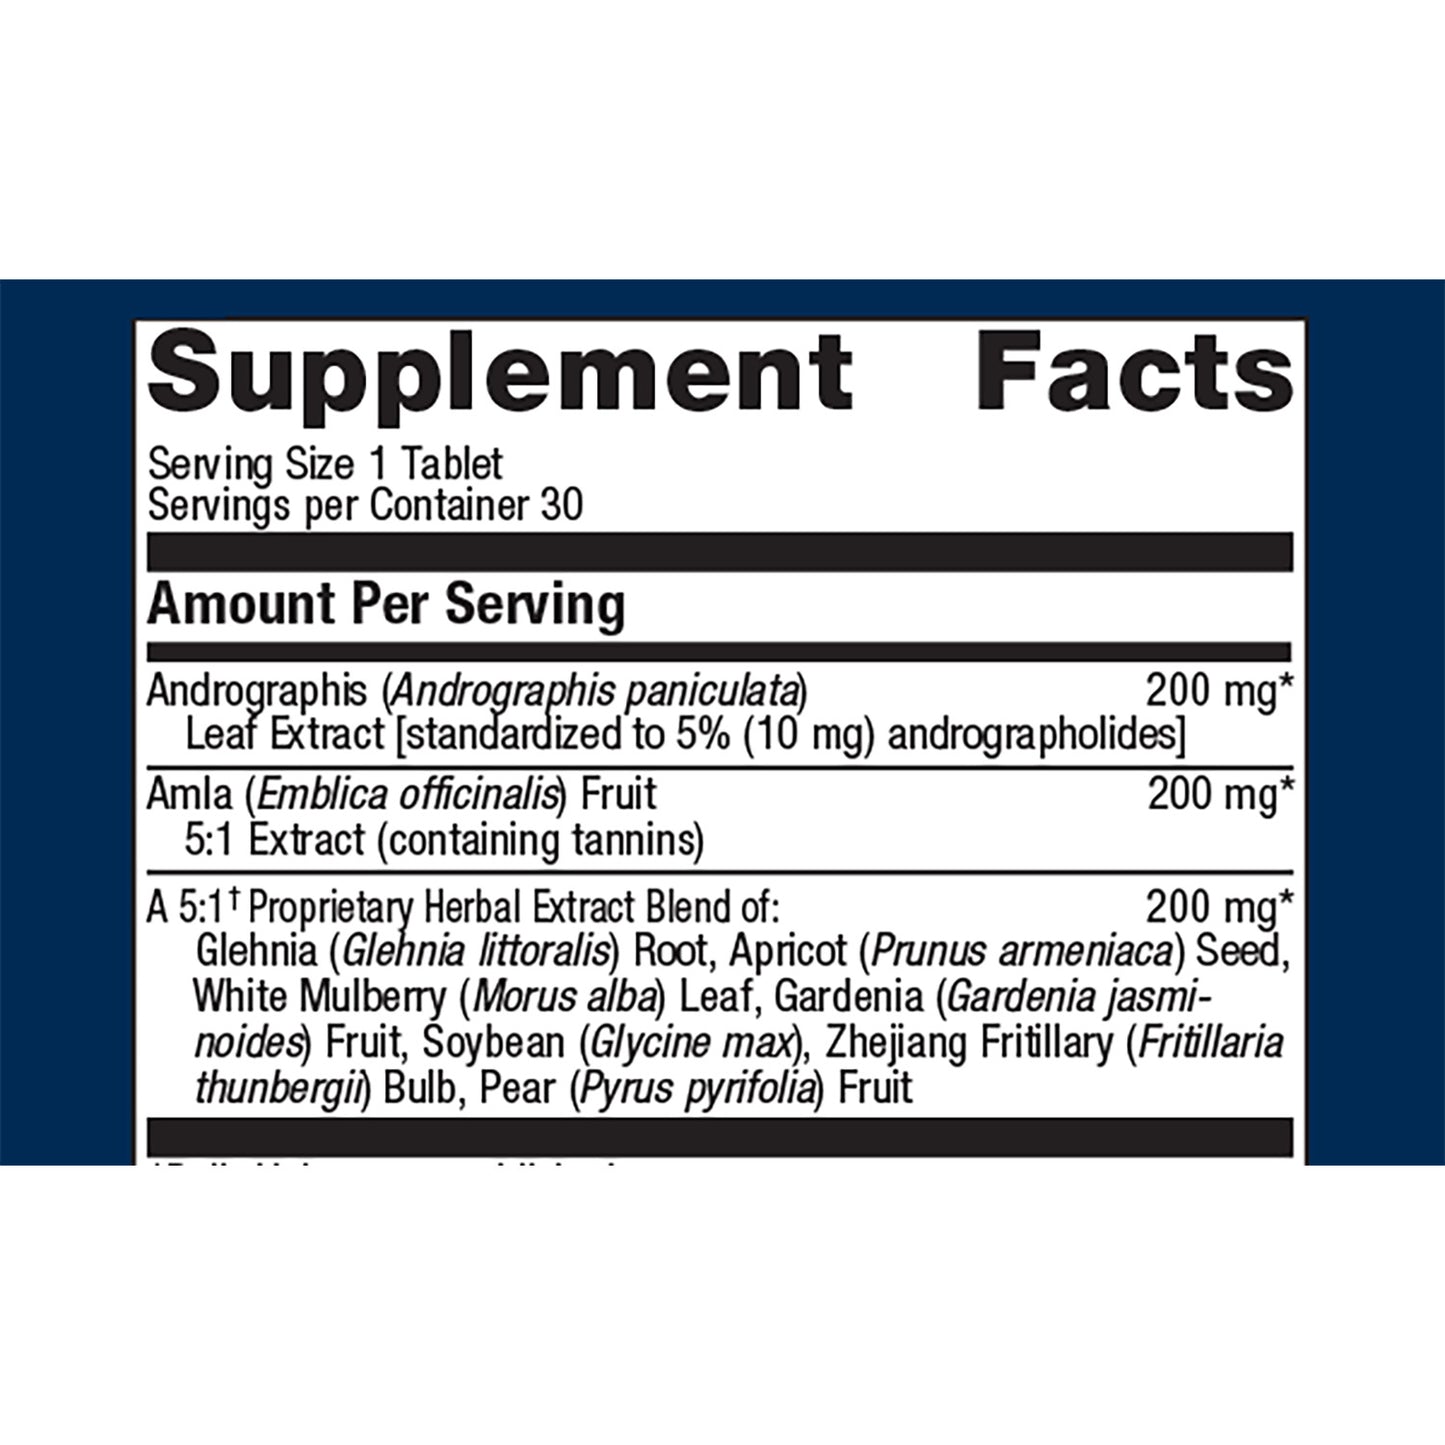

Andrographis Plus® delivers a proprietary blend of Ayurvedic and Asian herbs including concentrated andrographis extract and amla designed to support immune health. A proprietary herbal preparation traditionally used to support lung health rounds out this advanced immune support formula.

Ingredients: Microcrystalline cellulose, andrographis leaf extract, amla fruit extract, glehnia root extract, apricot seed extract, white mulberry leaf extract, gardenia fruit extract, soybean (soy), zhejiang fritillary bulb extract, pear fruit extract, cellulose, croscarmellose sodium, calcium silicate, stearic acid (vegetable), silica, magnesium stearate (vegetable), and coating (hypromellose, medium-chain triglycerides, and hydroxypropylcellulose). Contains: Soy.